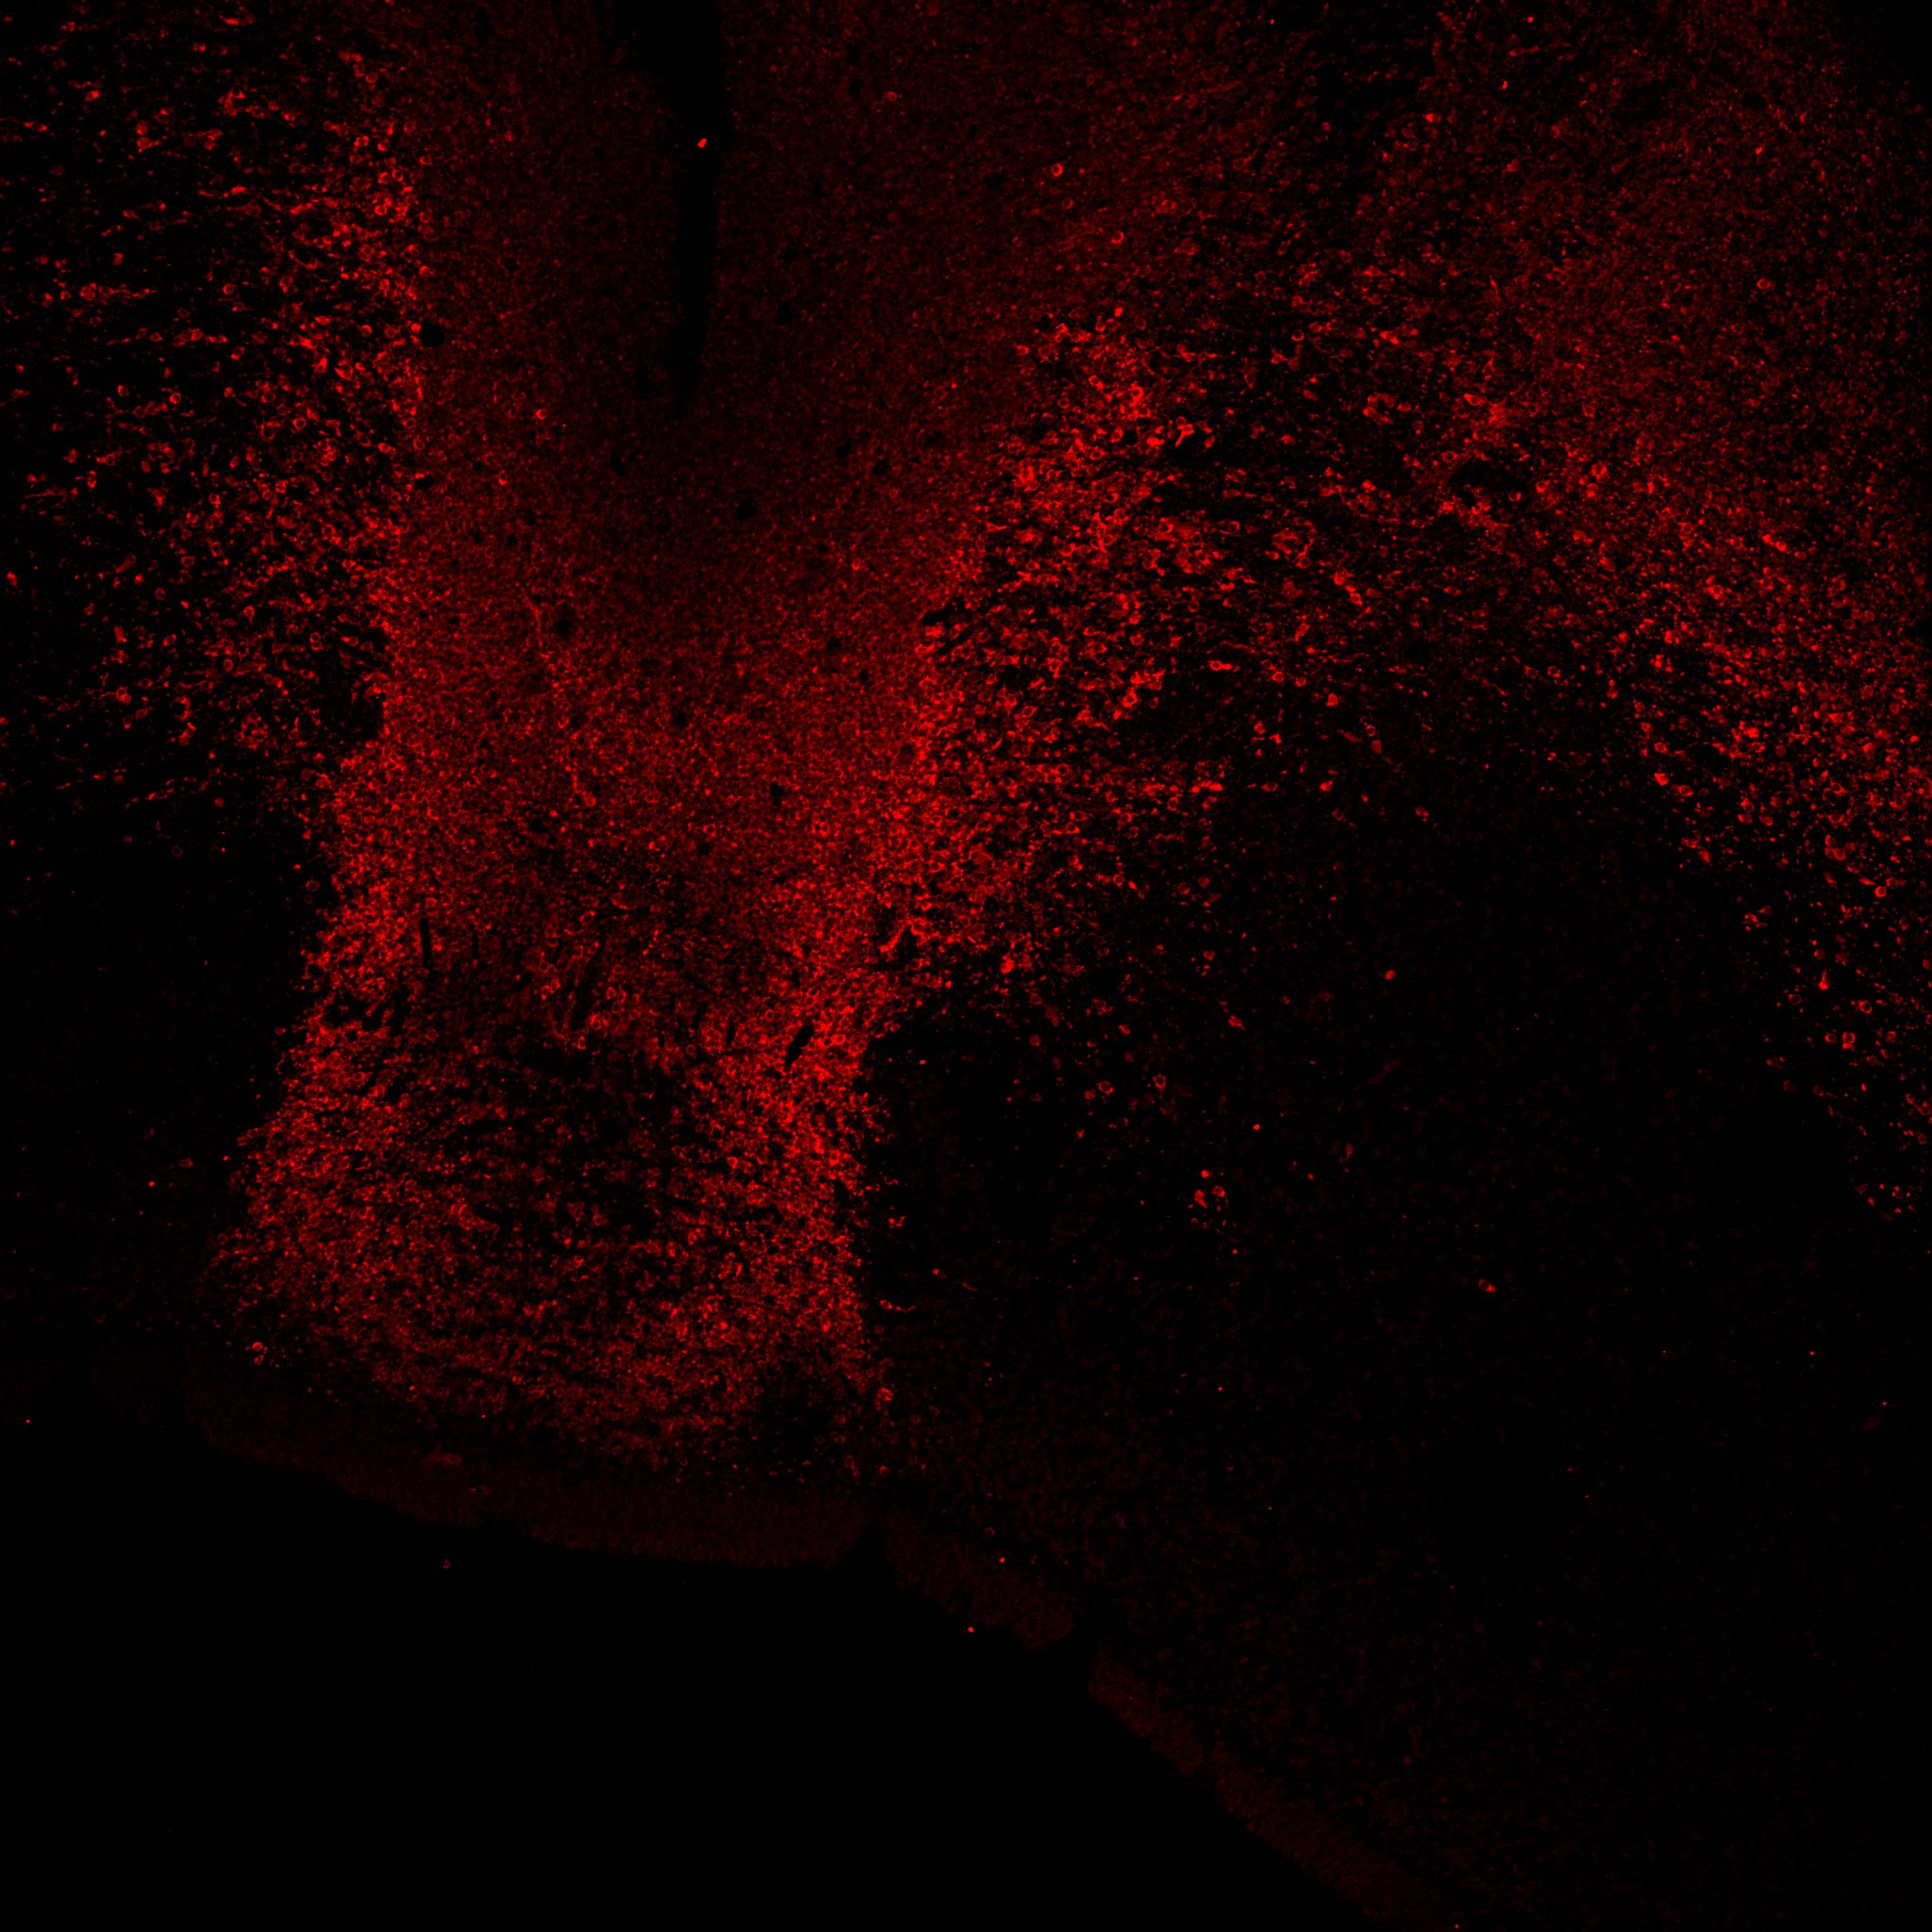

TH

11PCW human midbrain